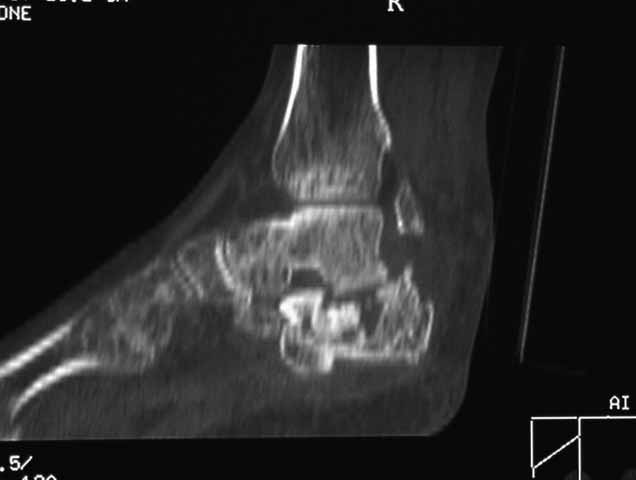

Данное исследование сделано в неправильной позиции стопы, стопа находится под прямым углом. Но несмотря на это, здесь можно увидеть, что латеральная стенка смещена, фиброз между фрагментами и варусное смещение пятки.

Топография зависит от позиции пятки в пространстве и неправильное положение закрывает обзор нужных структур. Важными структурами в исследовании пятки является задняя фасетка, бугор и боковые стенки. Существует специальные рентгенснимки, показывающие импинджмент с лодыжкой, а также положение бугра. Для КТ стопу надо инклинировать под 30 градусов, иначе можно пропустить важные переломы.

Нет срочности, но необходимо исправить варус и сделать субталарный артродез. Латеральное положение, расширенный доступ и closed wedge остеотомия с открытым кнаружи углом, возможно, удастся визуализировать через линию остеотомии недостающие части медиальной стенки - костный графт. Дистракция и после подготовки поверхности кости субталарный дистракционный артродез с помощью костного блока, взятого из крыла. Достаточно двух 6.5мм канюлированных шурупов из пяточного бугра медиально и латерально в направлении таранной кости. Из-за увеличения высоты стопы после артродеза кожа закрывается трудно, и могут быть краевые некрозы, которые лечатся долгими перевязками. Нужна предоперационная беседа по поводу задержки заживления, тогда больные встречают проблемы с пониманием.